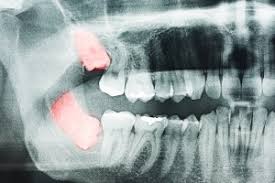

사랑니는 치아 중 가장 나중에 나고 자라므로 턱뼈에 공간이 부족하면 똑바로 나오지 못하고 주변의 잇몸을 괴롭히면서 통증을 유발한다고 한다.

▶사랑니가 똑바로 나지 않고 비스듬히 난 경우 ▶사랑니 주변 잇몸이 자꾸 붓고 아픈 경우 ▶사랑니와 그 앞 어금니 사이에 음식물이 자주 끼는 경우 ▶사랑니에 충치가 생겼으나 치료가 어려운 경우 ▶사랑니 앞의 어금니를 치료해야 하는데 사랑니로 인해 정상적인 치료가 어려운 경우 ▶교정치료를 해야 하는데 사랑니가 방해가 되는 경우 ▶X선 검사 소견 상 사랑니 주변에 혹으로 의심할 만한 부분이 나타난 경우 사랑니를 반드시 빼야 한다고 한다.

완전히 나오지 않은 사랑니를 빼는 건 복잡한 수술 중 하나라고 한다.

하악골(아래턱뼈) 속에는 입술과 잇몸의 감각을 느끼게 하는 신경이 지난다고 한다.

상악골(위턱뼈) 속에는 축농증이 일어날 수 있는 부분인 상악동이 있다고 한다.

이들이 사랑니 뿌리와 근접하거나 겹쳐 있는 경우가 종종 있다고 한다.

이때는 콘빔형전산화단층촬영(CBCT)을 포함한 사전 검사와 평가 후 수술을 받는 것이 좋다고 한다.